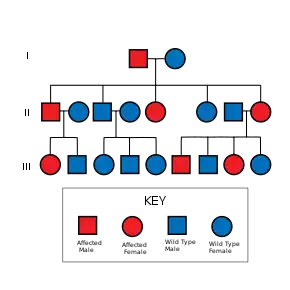

The presence of all of these hallmarks is not needed for a diagnosis. A clinical diagnosis is considered made when, with lentigines present there are 2 other symptoms observed, such as ECG abnormalities and ocular hypertelorism, or without lentigines, 3 of the above conditions are present, with a first-degree relative (i.e. parent, child, sibling) with a clinical diagnosis.[6]

It is recommended that those with the syndrome who are capable of having children seek genetic counseling before deciding to have children. As the syndrome presents frequently as a forme fruste (incomplete, or unusual form) variant, an examination of all family members must be undertaken.[13] As an autosomal dominant trait there is a fifty percent chance with each child that they will also be born with the syndrome. Although fully penetrant, since the syndrome has variable expressivity, one generation may have a mild expression of the syndrome, while the next may be profoundly affected.